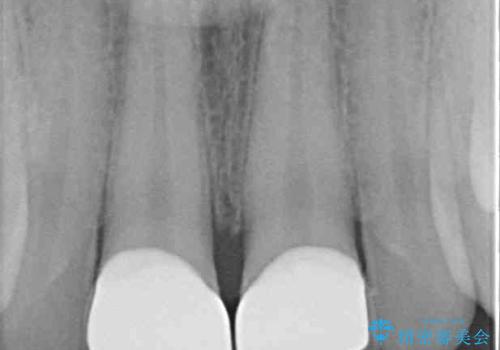

無菌的環境下にて歯の状態を調べ、最終的にオールセラミッククラウンにて補綴治療を行うこととしました。

幸いにも神経組織に影響はなく、健全な状態で治療を終えることができました。

外傷歯は、将来的に歯根吸収を起こす可能性があるため、定期的なレントゲン撮影により経過観察が必要となります。